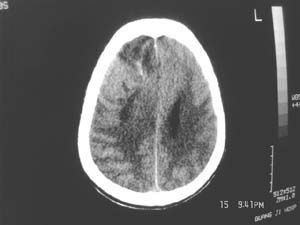

女,60岁,反复头痛3天,呕吐3小时伴昏迷10分钟入院检查。

右额叶占位,有占位效应,中线偏移,病灶位于镰旁,呈囊实性并有钙化,

考虑:1.脑膜瘤。2.胶质瘤。

理由:1.病灶位于前颅凹及镰旁,有明显占位效应---支持脑膜瘤。

2.病灶呈囊实质性并有条状钙化,符合胶质瘤改变;

另外也不排除包虫病的可能。

右额叶占位,有占位效应,中线偏移,病灶位于镰旁,呈囊实性并有钙化 kaolv  少枝胶质瘤。胶质瘤。

病变范围较大,累及左额叶,内见钙化。及高密度灶。考虑;胶母伴卒中可能大。